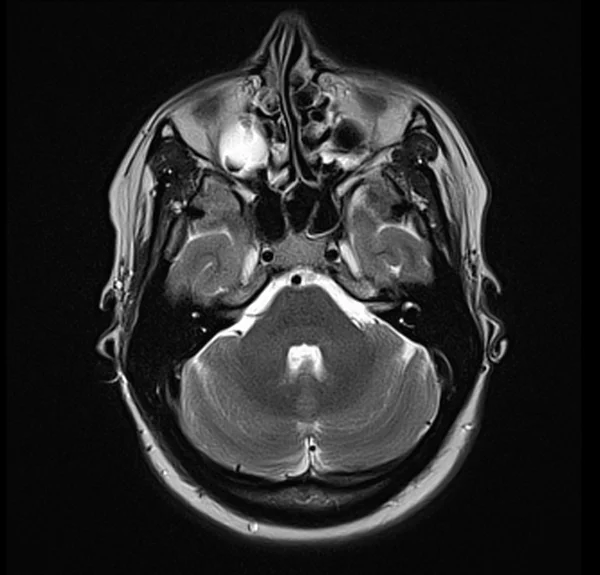

Brain MRI T2 axial images